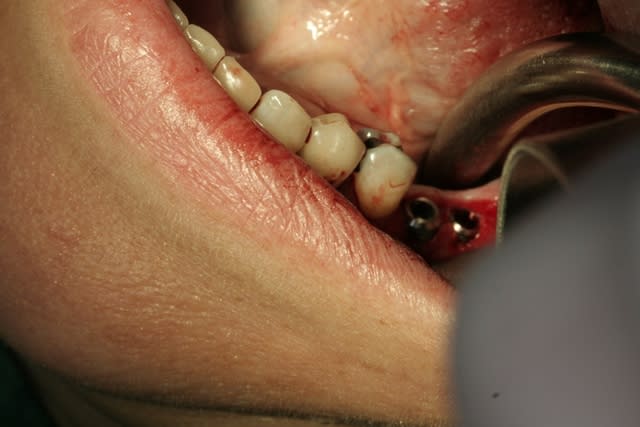

voilà un ptit cas de...disons 23 bis...car double agénésies des latérales...pas trop mal compensée naturellement secteur 1...mais persistance de la 63...à bout de souffle...

cette petite patiente ne veux pas d'ODF...mais ne veux pas rester sans dent...d'où cette intervention...avec la pose d'1 implant, avec expansion à l'aide de mon kit MIS... et mise en vitrine immédiate...

aucun...juste mon point d'injection de l'anesthésie locale...;-))

intervention totale flapless...y devrais pas trop y avoir de suites op...;-))

en effet...l'expansion au moteur...çà change tout...;-))